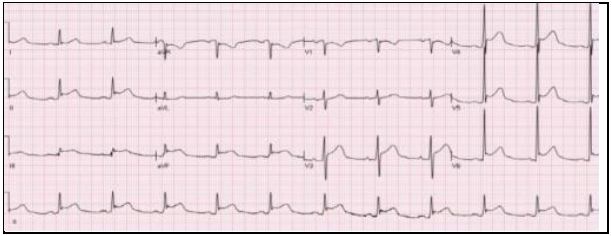

Leia o cas9 clínico que segue para responder às questões 72 a 74.

Um jovem previamente hígido de 22 anos dá entrada na emergência com dor em pontada no hemitórax esquerdo e febre após 3 dias de um quadro de gastroenterocolite aguda. Ao exame físico, apresentava com FC = 70bpm, PA 100x60mmHg e Temp. 37,8°. A dosagem laboratorial de troponina foi de 2.000ng/ml (VR < 0,04ng/ml) e o eletrocardiograma foi o seguinte:

Nesse caso, o tratamento adequado é o da indicação de

Leia o cas9 clínico que segue para responder às questões 72 a 74.

Um jovem previamente hígido de 22 anos dá entrada na emergência com dor em pontada no hemitórax esquerdo e febre após 3 dias de um quadro de gastroenterocolite aguda. Ao exame físico, apresentava com FC = 70bpm, PA 100x60mmHg e Temp. 37,8°. A dosagem laboratorial de troponina foi de 2.000ng/ml (VR < 0,04ng/ml) e o eletrocardiograma foi o seguinte:

Qual dos exames a seguir deverá ser solicitado nesse caso?

Leia o cas9 clínico que segue para responder às questões 72 a 74.

Um jovem previamente hígido de 22 anos dá entrada na emergência com dor em pontada no hemitórax esquerdo e febre após 3 dias de um quadro de gastroenterocolite aguda. Ao exame físico, apresentava com FC = 70bpm, PA 100x60mmHg e Temp. 37,8°. A dosagem laboratorial de troponina foi de 2.000ng/ml (VR < 0,04ng/ml) e o eletrocardiograma foi o seguinte:

O quadro clínico apresentado sugere como diagnóstico: